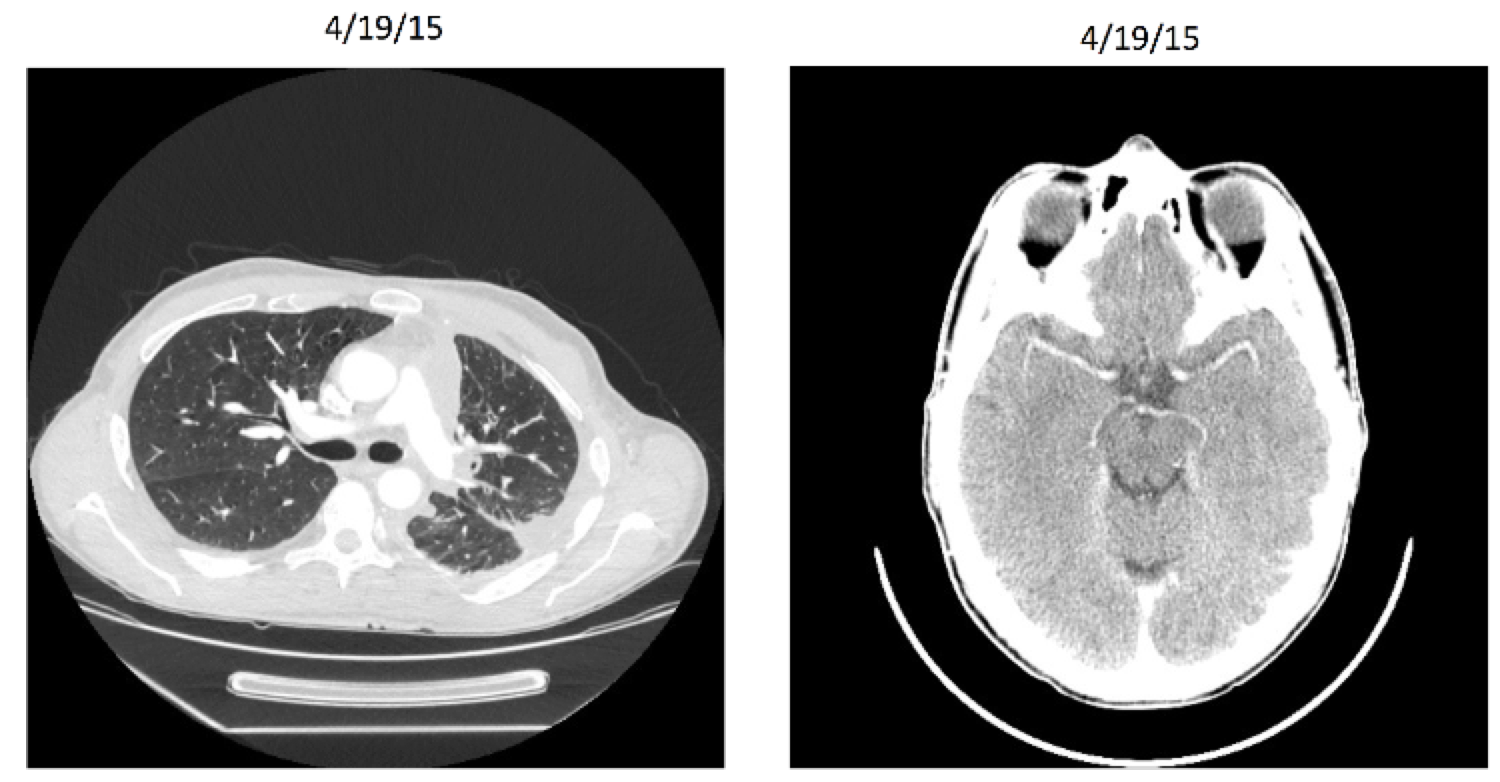

Entrectinib: Patient X Before

Entrectinib: Patient X After

Entrectinib

Targeted therapy (NTRK gene rearrangement)

Very stringent inclusion/exclusion criteria

Effective for other histologies (including breast, colorectal, and neuroblastoma)

8/11 responders for lung cancer in initial study